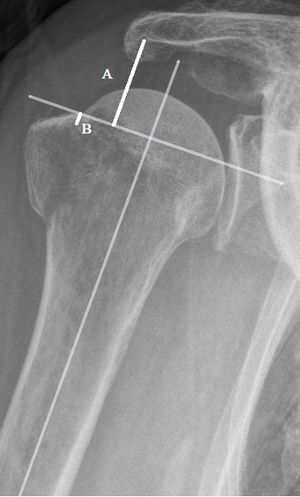

Critical Shoulder Angle

In addition to the morphology or size of the acromion, the variation of the inclination of the glenoid is a radiographic marker that may indicate rotator cuff lesions. Thus, several studies show a relationship between a high glenoid tilt and the upper migration of the humeral head.[50][51] This migration favors subacromial compression of the supraspinatus and therefore tendon tears. In 2013, Moor et al. describe a new radiological marker, the critical shoulder angle.[9] The interest is to include in one measure the concept of the acromial index and the glenoid inclination. It is represented by the angle between a line connecting the upper and lower pole of the glenoid and another connecting the lower pole of the glenoid with the lateral edge of the acromion (Figure). It demonstrates an association between a tear of the cuff and a critical shoulder angle greater than 35 degrees and inversely an association between an osteoarthritis and a critical shoulder angle of less than 30 degrees. Gerber et al. confirm this relationship in a biomechanical study.[52] They show that the increase in critical shoulder angle is associated with an increase in shear forces, especially in degrees of mobility associated with a large number of activities of daily life. The result is a greater antero-superior instability involving more necessary activity on the part of the supraspinatus to stabilize the shoulder and leading more easily to tears. These theories and the association between critical shoulder angle, osteoarthritis and tear of the cuff are also demonstrated significantly in more recent studies.[53][54][55][56][57][58] Engelhardt et al. even independently analyzed the three different parameters (acromial index, IG, critical shoulder angle) demonstrating that critical shoulder angle is the best parameter for estimating the risk of rotator cuff injury.[45] This can be explained by the fact that it combines the influence of a GI and a high acromial index on the upper migration of the humeral head. However, he does not find this precision when it comes to correlating the critical shoulder angle with osteoarthritis. More recently, Chalmers et al. have achieved less satisfactory results.[59] They obtained differences of up to 2 degrees, but too low to have a significant association on the presence of a tendinopathy of the cuff. Since the critical shoulder angle is a radiological measure, it is important to have a good correlation of the measurement. Bouaicha et al. demonstrated in their study that the correlation between anteroposterior standard radiography and scanner is very satisfactory and that the differences that can occur between these two modalities are quite negligible.[60] Spiegl et al. and Cherchi et al. demonstrate a good intra- and inter-observer correlation in the radiological analysis of the critical shoulder angle.[57][58] However, Suter et al. describe the measurement of the critical shoulder angle as a function of the spatial relationship of the scapula as a function of the radiological monitor.[61] They thus note that the critical shoulder angle is sensitive to the ante or retro-version of the scapula relative to the radiological monitor, with a change from 5 to 8 degrees which can change the critical shoulder angle measurement by 2 degrees and thus influence the clinical interpretation.